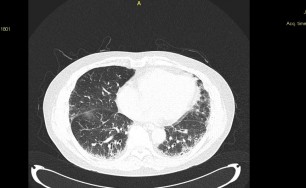

숨케어한의원에서는 전화예약을 받고 있습니다. 내원시 엑스레이, CT사진, 폐기능검사지를 가지고 오시면 자세한 상담이 가능합니다.